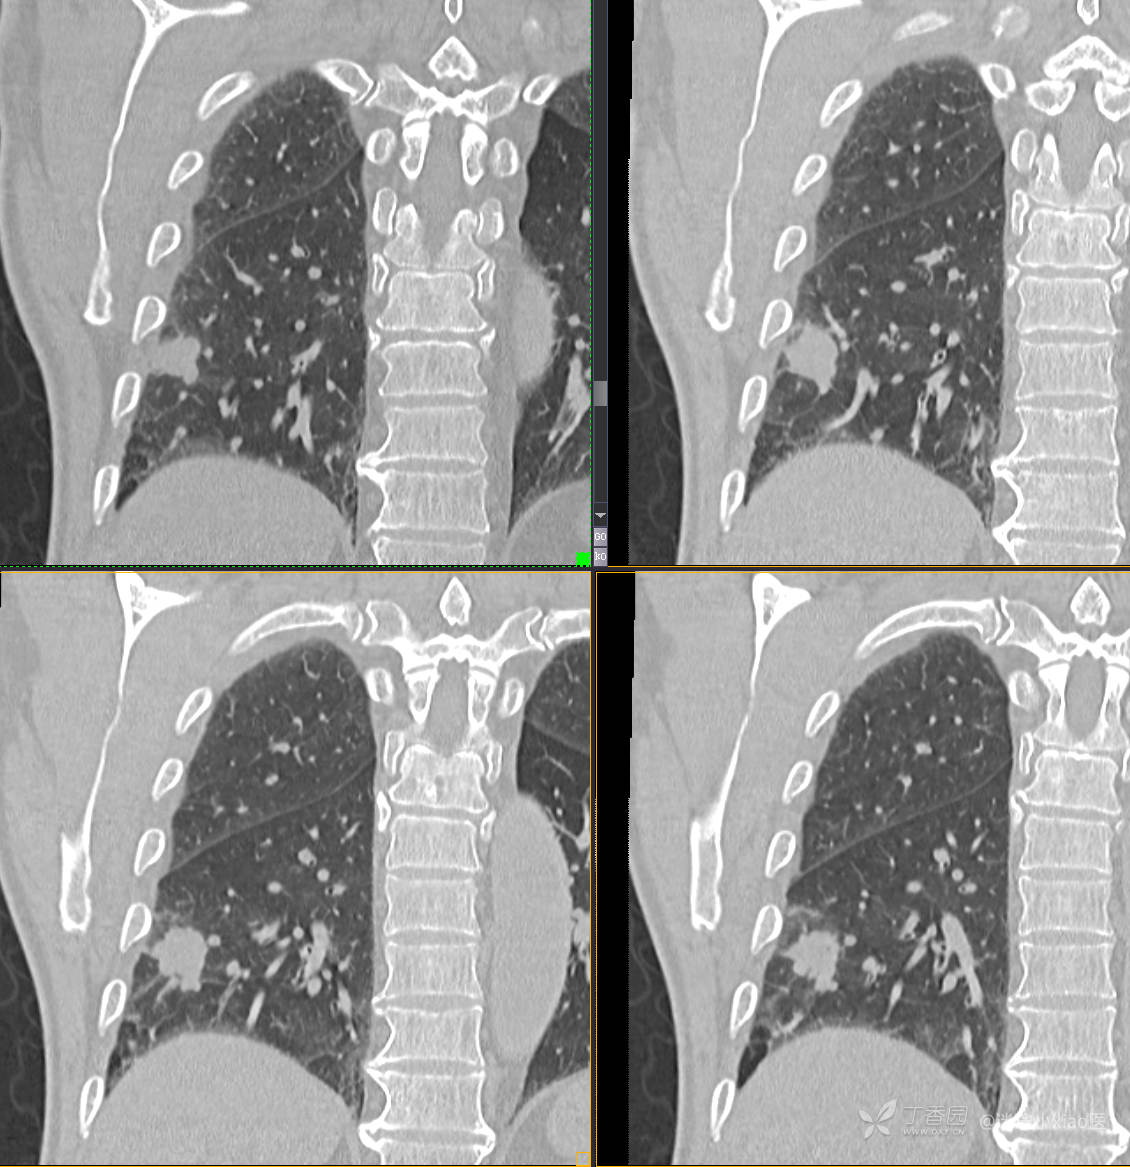

胸组50:老年男性,发现肺占位一天,(结果公布)

主诉: 发现右肺占位1天

现病史: 患者诉1日前在当地医院检查时胸部CT示;肺结节(具体不详),当时无胸闷气急。 无咳嗽咳痰,无胸痛,无恶心呕吐等。今为求进一步治疗,门诊拟“肺结节”收治入院。病来,患者神志清,精神可,胃纳睡眠可,二便无殊,体重无明显增减。